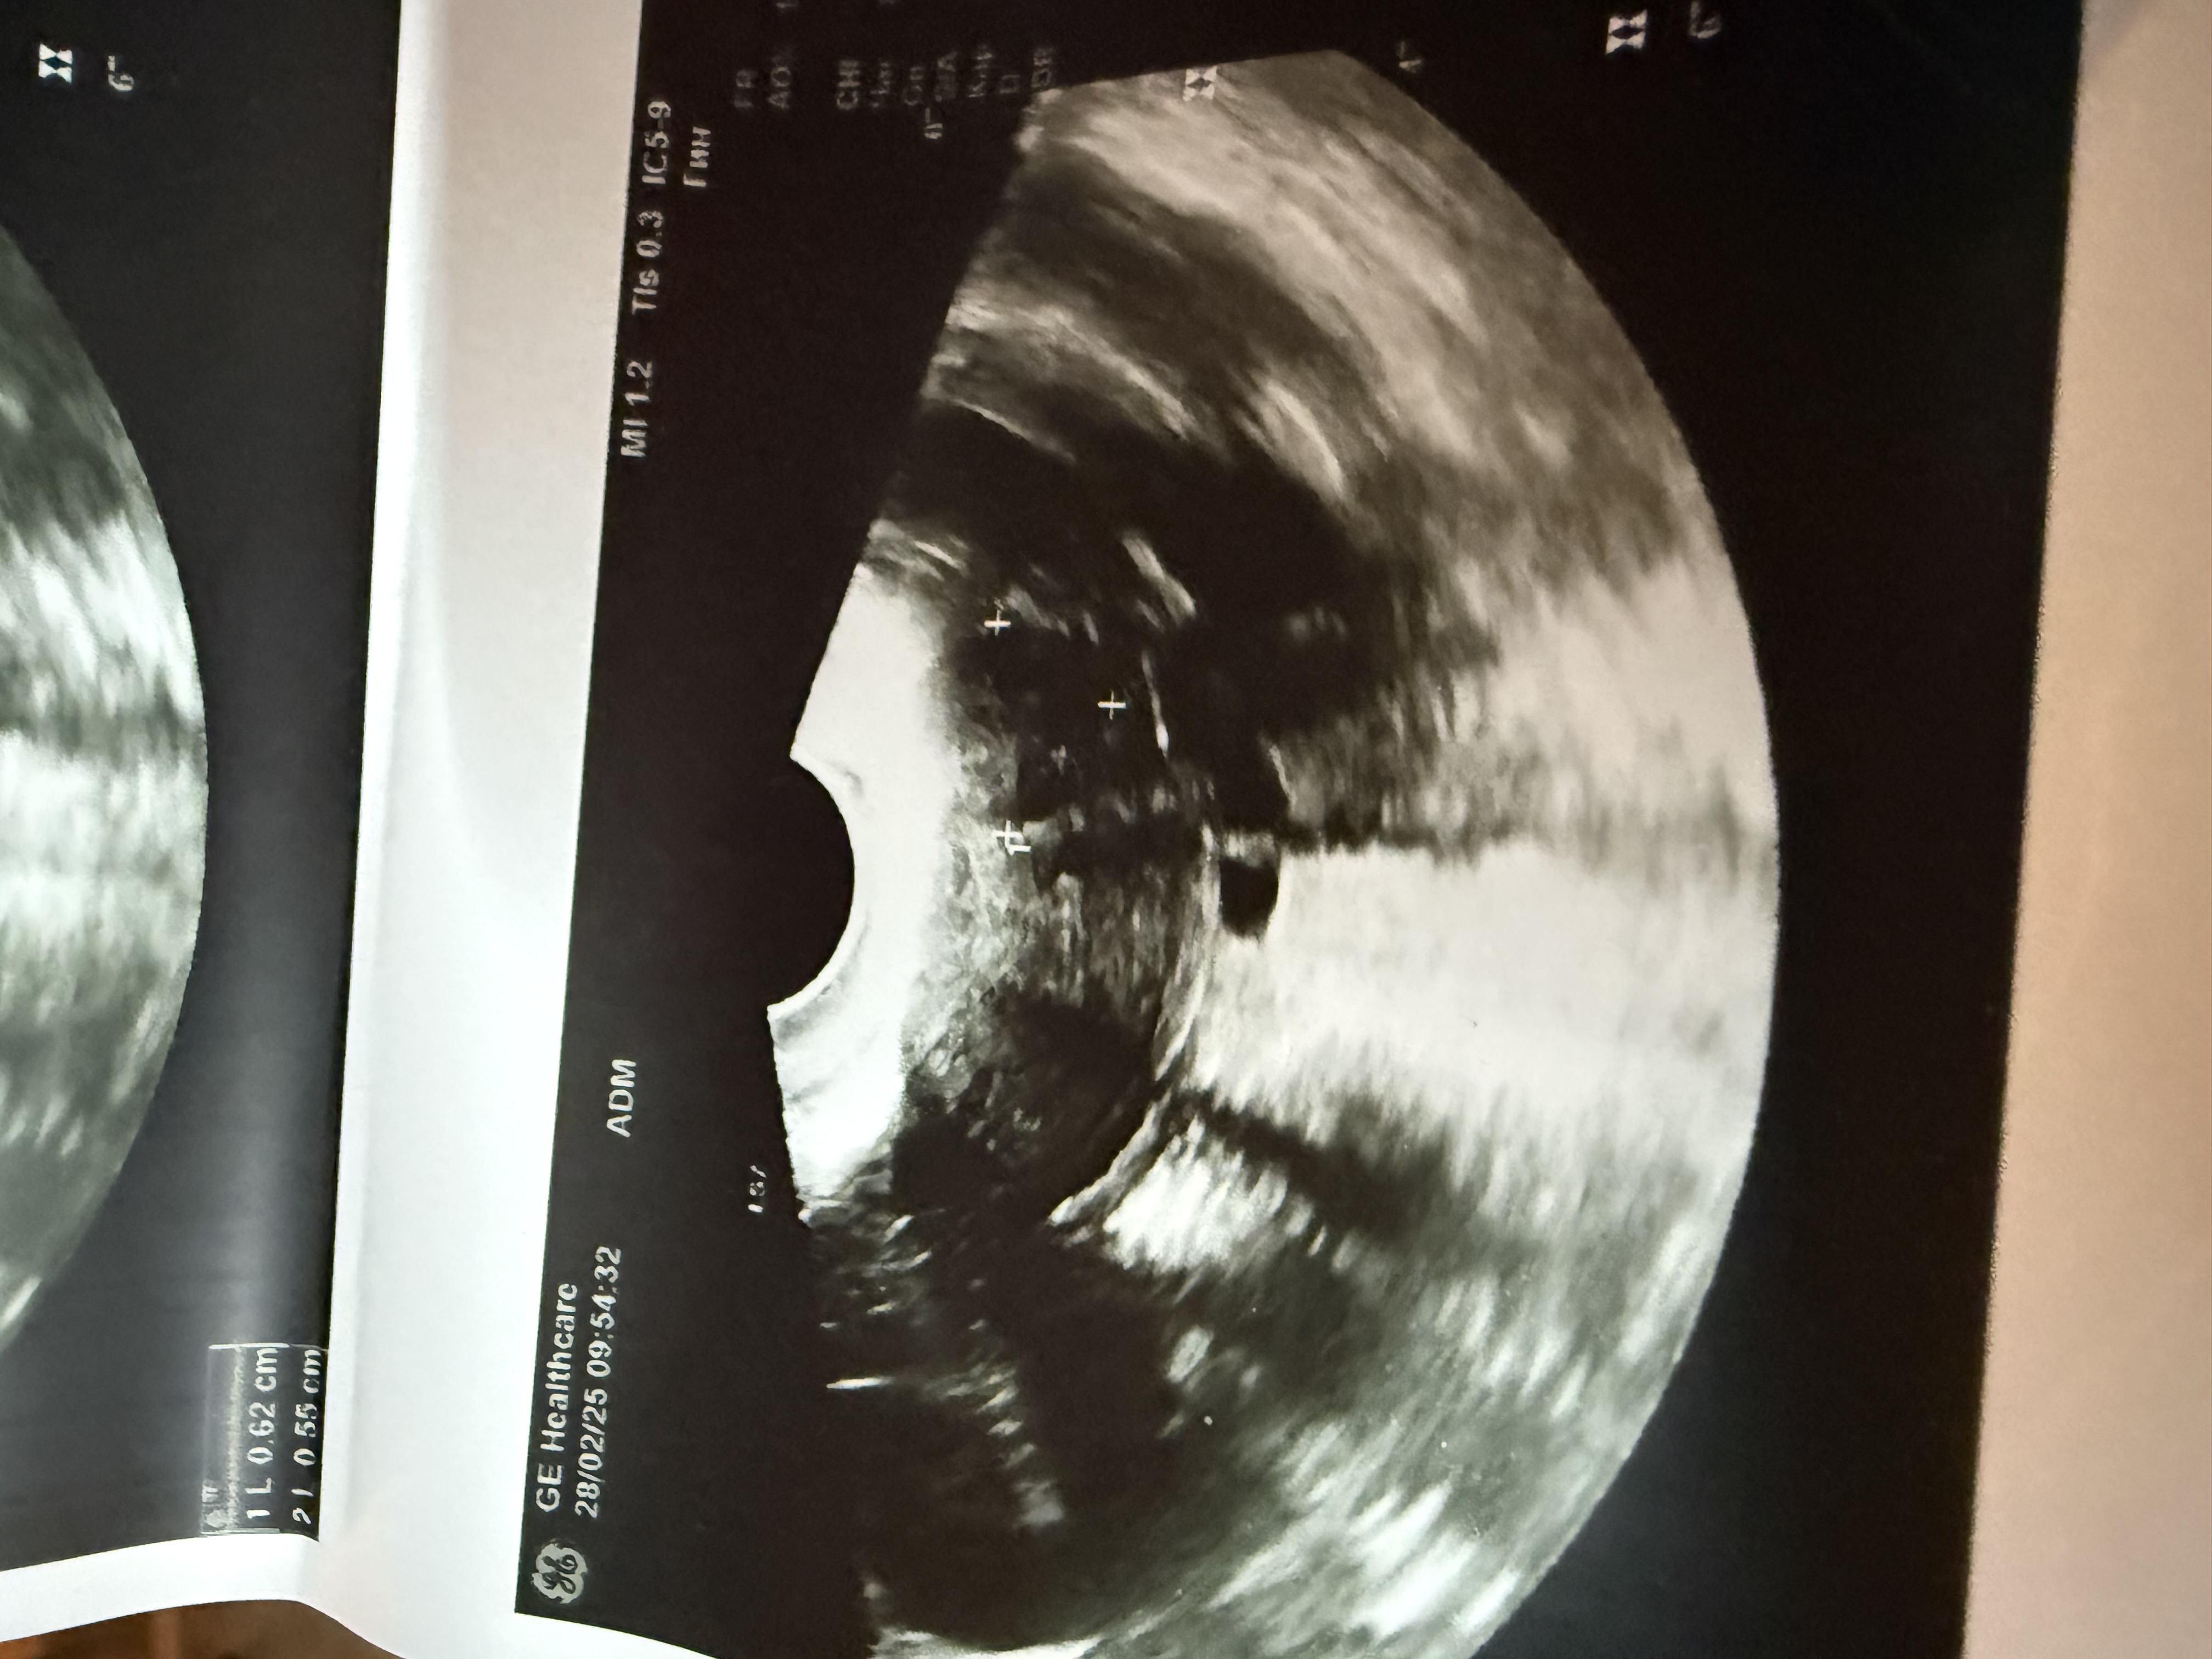

Изображение Изображение Изображение

Ольга Забелина, картина и вправду странная... Экспертное узи и хгч в динамике, все что можно посоветовать. Скорее сорвалась б.

Ольга Забелина, 3 дня назад на узи не было этого шарика